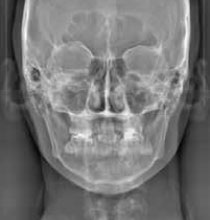

セファロ(正面)

低被ばくで、広い範囲の撮影が可能なCT(3D撮影)機器です。デジタル方式ですので、被ばく量が従来のものと比べ各段に軽減されています。

3D撮影ができることにより、多角的な診断が可能となり、インプラント治療などにおける診断をはじめ、複雑な治療である親知らずの抜歯や根管治療を安全に、且つより正確に行うことが可能です。